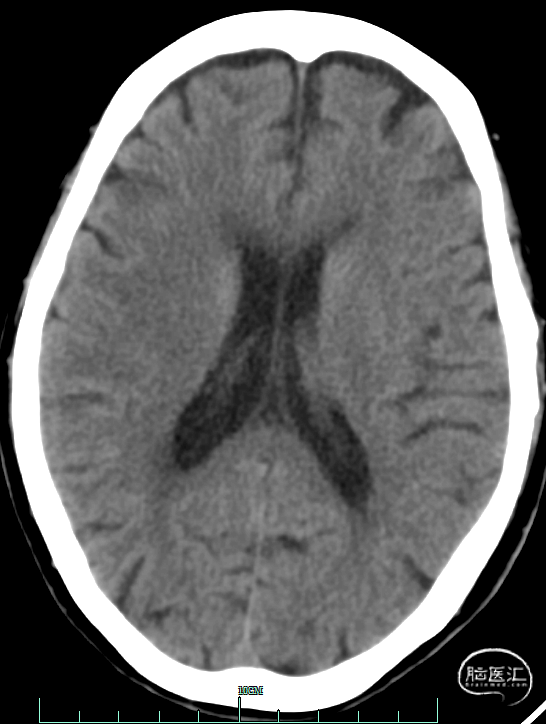

术前影像资料